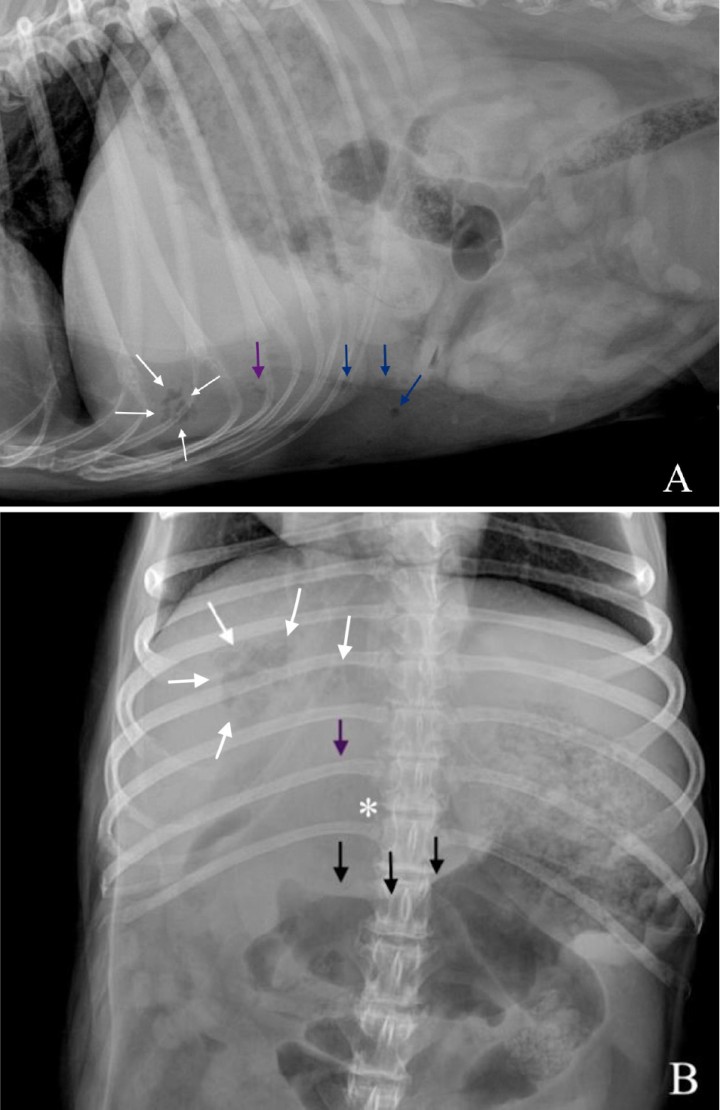

Se observa una disminución de la visualización de las serosas abdominales en el abdomen craneal y medio (Fig. 2), con presencia de pequeñas burbujas de gas libre caudoventral a la silueta hepática compatible con neumoperitoneo (Fig. 2A). Ambas proyecciones mostraban una hepatomegalia con bordes redondeados excediendo levemente el arco costal, con presencia de una zona de opacidad gas, de morfología y bordes irregulares, poco definidos, localizada en la zona de proyección hepática en su aspecto craneoventral y con lateralización hacia la derecha (Fig. 2). Así mismo, se apreció otra lesión, de opacidad gas y de menor tamaño, caudalmente a la previamente descrita, en la zona media del hígado y asociada a un efecto masa en la proyección ventrodorsal, que producía hacia caudal un desplazamiento del cuerpo gástrico y antro pilórico (Fig. 2B). Como hallazgo incidental, se observó una espondilosis ventrolateral deformante en la columna lumbar.

<p>Imágenes ampliadas de las radiografías en proyección lateral izquierda (<strong>A</strong>) y ventrodorsal (<strong>B</strong>). Se observa la lesión de opacidad gas y bordes irregulares localizada en la proyección hepática, en su aspecto craneoventral y lateralizada a la derecha (flechas blancas). Se muestra otra lesión de opacidad gas, de menor tamaño respecto a la descrita, en la zona media del hígado (flechas moradas), que provoca un efecto masa (*) y genera un desplazamiento hacia caudal del antro pilórico y cuerpo gástrico (flechas negras). Caudoventral a la silueta hepática se observan pequeñas burbujas de gas libre compatible con neumoperitoneo (flechas azules).</p>

Imágenes ampliadas de las radiografías en proyección lateral izquierda (A) y ventrodorsal (B). Se observa la lesión de opacidad gas y bordes irregulares localizada en la proyección hepática, en su aspecto craneoventral y lateralizada a la derecha (flechas blancas). Se muestra otra lesión de opacidad gas, de menor tamaño respecto a la descrita, en la zona media del hígado (flechas moradas), que provoca un efecto masa (*) y genera un desplazamiento hacia caudal del antro pilórico y cuerpo gástrico (flechas negras). Caudoventral a la silueta hepática se observan pequeñas burbujas de gas libre compatible con neumoperitoneo (flechas azules).

La pérdida de diferenciación de serosas fue compatible con un leve volumen de líquido libre abdominal o inflamación peritoneal, sin poder descartar otras causas como una carcinomatosis/sarcomatosis peritoneal. Las causas más comunes de neumoperitoneo incluyen heridas penetrantes, fuga de gas de órganos enfisematosos, perforación o rotura de órganos que contienen gas debido a traumatismos, neoplasias o ulceraciones y por causas iatrogénicas, (p. ej., laparotomías).[ Dennis R, Kirberger R, Barr F, et al. Other abdominal structures: abdominal wall. peritoneal and retroperitoneal cavities. parenchymal organs. En: Dennis R, Kirberger R, Barr F, eds. Handbook of Small Animal Radiology and Ultrasound – Techniques and Differential Diagnoses. 2nd ed. Croydon: Saunders Elsevier; 2010; 229-266. ] La lesión localizada en la proyección hepática más cranealmente y lateralizada hacia la derecha con contenido gas, según su localización, podría ser compatible con un absceso hepático, colecistitis enfisematosa, neoplasia o granuloma hepático infectado. La lesión localizada más caudalmente y con efecto masa a nivel gástrico podría corresponderse con otro absceso o con la presencia de una masa necrosada de origen benigno (p. ej., hiperplasia nodular, quiste, hematoma) o maligno (p. ej., carcinoma hepatocelular).

Ante el conjunto de los hallazgos radiológicos encontrados, la sospecha principal fue de una rotura de un absceso/neoplasia hepática necrosada.